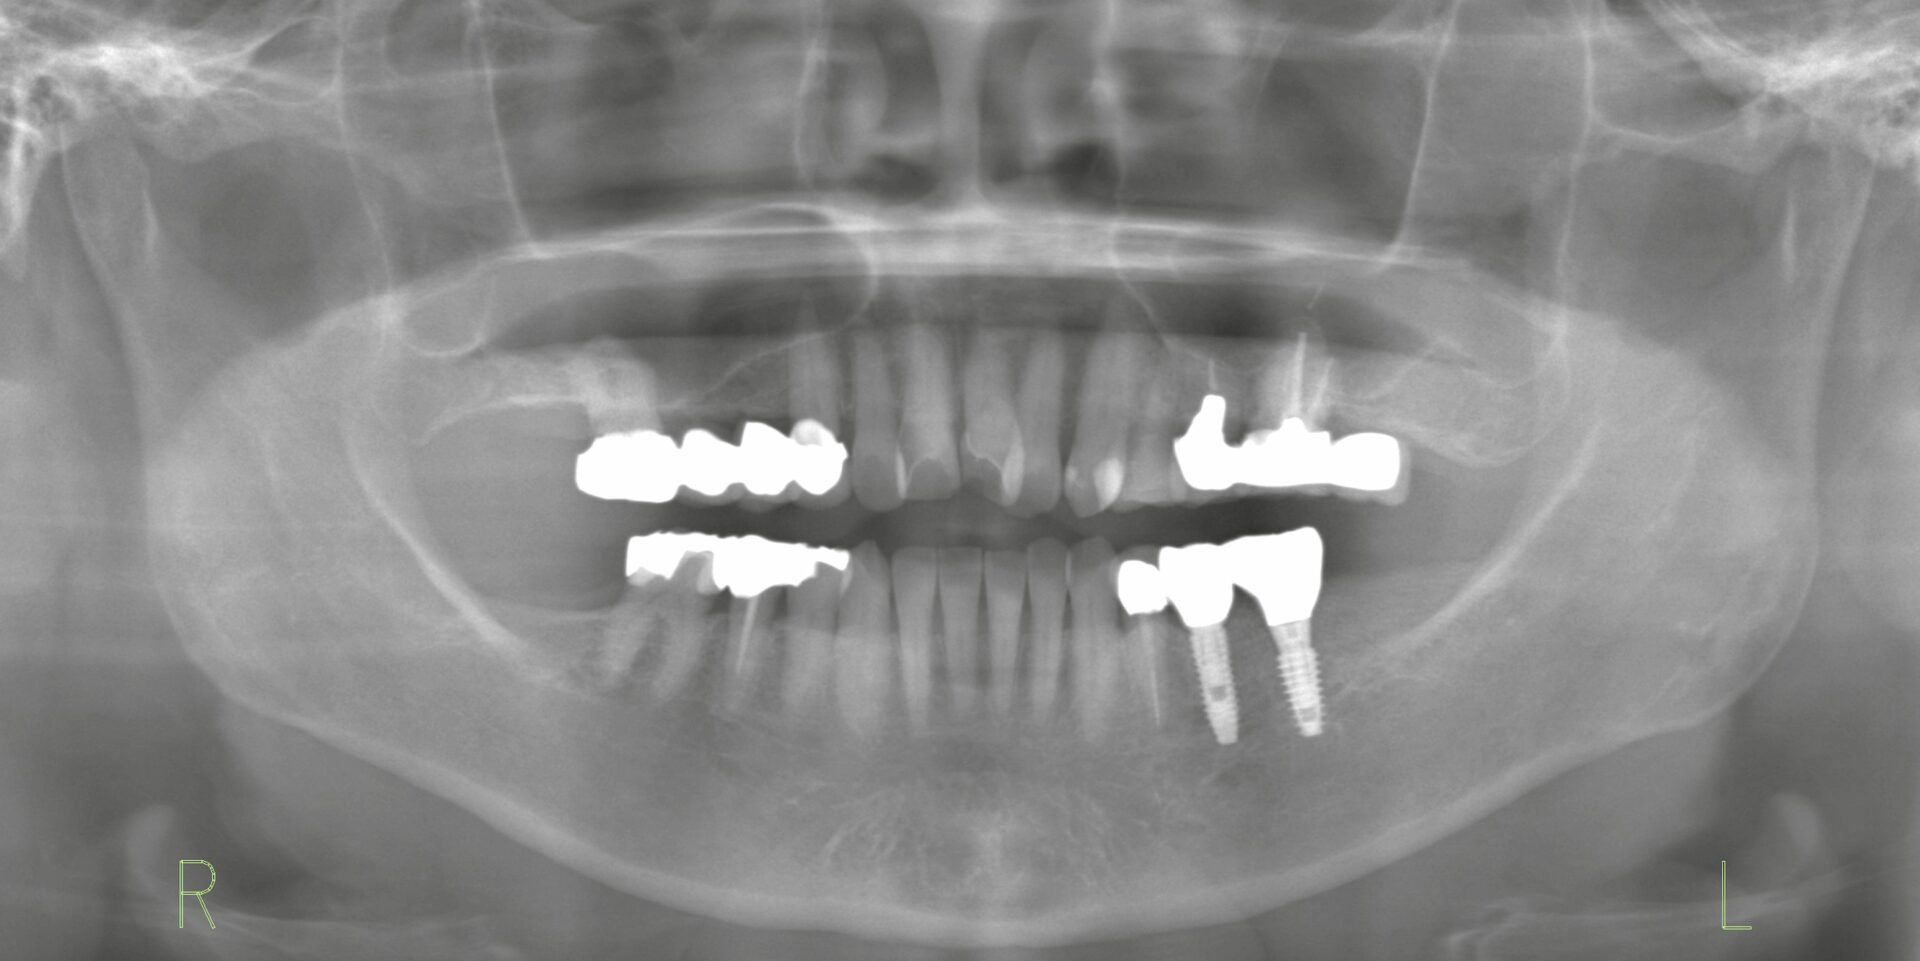

初診時のレントゲン

支台歯に動揺と排膿を認め、延長ブリッジは破折していました。延長ブリッジは「失活歯を支台として負担がかかる」ため、破折や歯周病リスクが高い治療方法の一つです。今回は抜歯が適応となり、延長ブリッジを撤去しました。